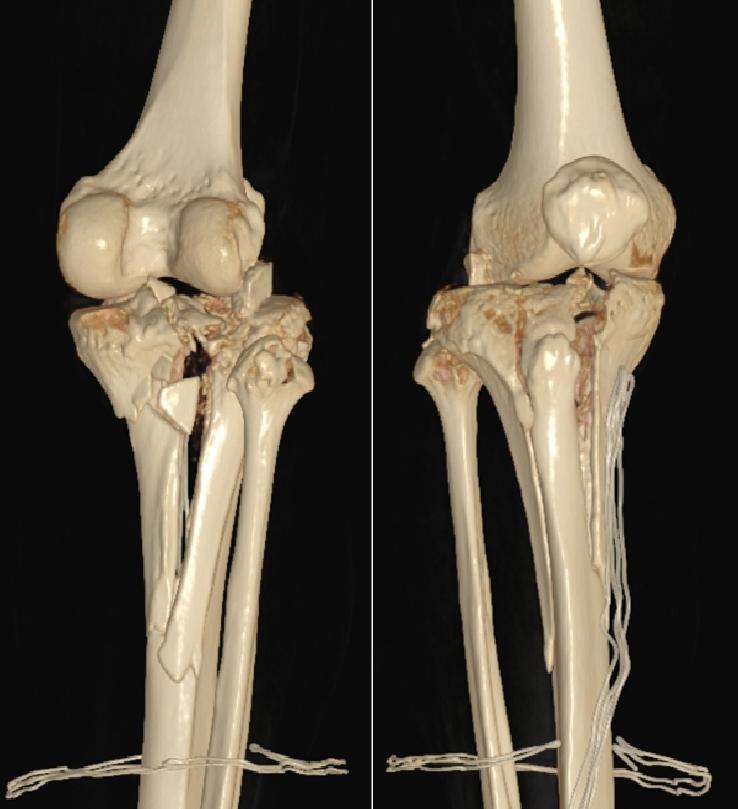

胫骨平台爆裂性粉碎,复位难度大

入院完善相关检查后,广州和平骨科医院骨科中心学科带头人赵洪普教授组织医师团队进行了全科术前讨论,为王先生制定了详细的手术和康复治疗方案。

“这类骨折本身就非常复杂,像打碎的瓷器,想要复原难度非常大。”赵洪普教授解释,“从检查结果来看,王先生的胫骨平台呈爆裂性粉碎,关节面碎裂、塌陷严重,同时合并外侧半月板撕裂、内侧副韧带断裂。而且,患者本身有高血压,术中止血和术后感染防控都是很大的考验。我们的手术目标不仅是把骨头拼回去,更要最大限度恢复未来关节功能,避免创伤性关节炎,这对术者的技术水平要求非常高。”